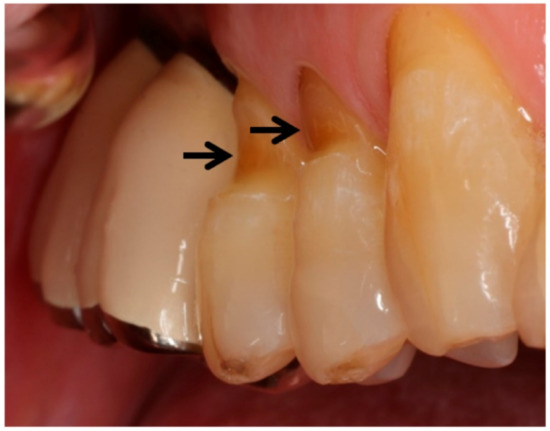

일단 여러 곳에 보철이 올려져 있었으며

군데군데 쌓여 있는 치석과, 부식된 치아들이 눈에 띄었습니다.

특히 앞니 절단 부분은 파절이 일어나 있었으며

이와 더불어 '치경부 마모증'도 관찰되고 있네요.

이 중에서 이시림의 원인으로 유력한 것은 어떤 것일까요?